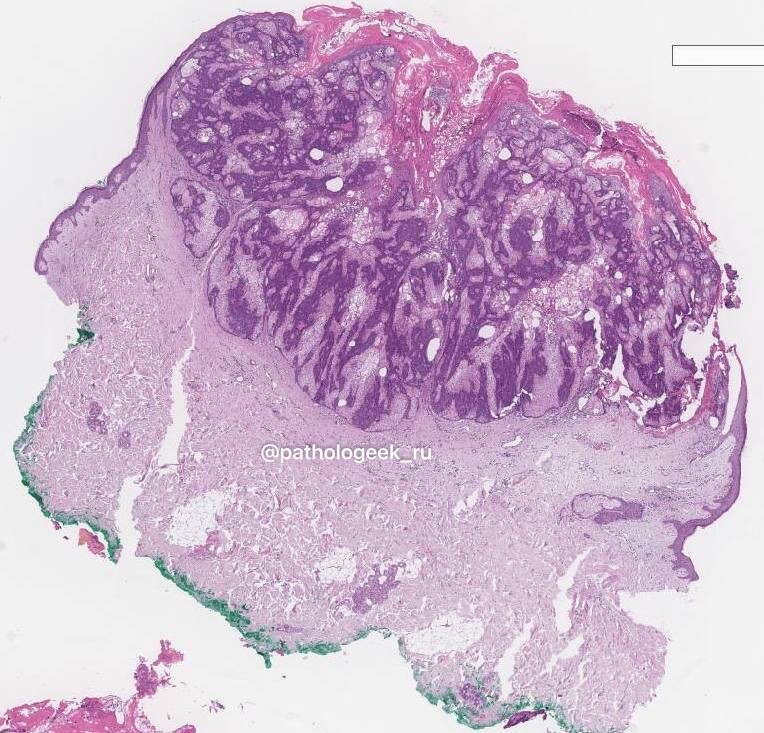

Микро

Себацеома – это узел в дерме с различной степенью вовлечения эпидермиса, который представлен хорошо отграниченными дольками, состоящими по большей части из мономорфных незрелых базалоидных клеток в сочетании с небольшим количеством зрелых себоцитов (<50%), беспорядочно рассеянных по всей опухоли. У зрелых себоцитов большое количество цитоплазматических вакуолей, которые придают ядру фестончатый вид. Могут присутствовать протоково-подобные структуры и кисты, которые часто характеризуются оэзинофильной кутикулой и иногда демонстрируют голокриновый тип секреции. Так же могут наблюдаться воронкоподобные структуры, плоскоклеточная метаплазия и апокриновая дифференцировка. Базалоидные клетки – активно делящиеся эпителиальные клетки, поэтому допускается высокая митотическая активность, о которой не следует волноваться. Однако патологических митозов и некрозов быть не должно. Были описаны разнообразные паттерны роста: ретикулярный/с мелким рельефом («рифленый»), крибриформный, синусоидальный/лабиринтный, с признаками по типу телец Верокаи, карциноид-подобный и железисто-подобный варианты. Иногда даже в пределах одной опухоли. При этом клинические проявления остаются неизменными.